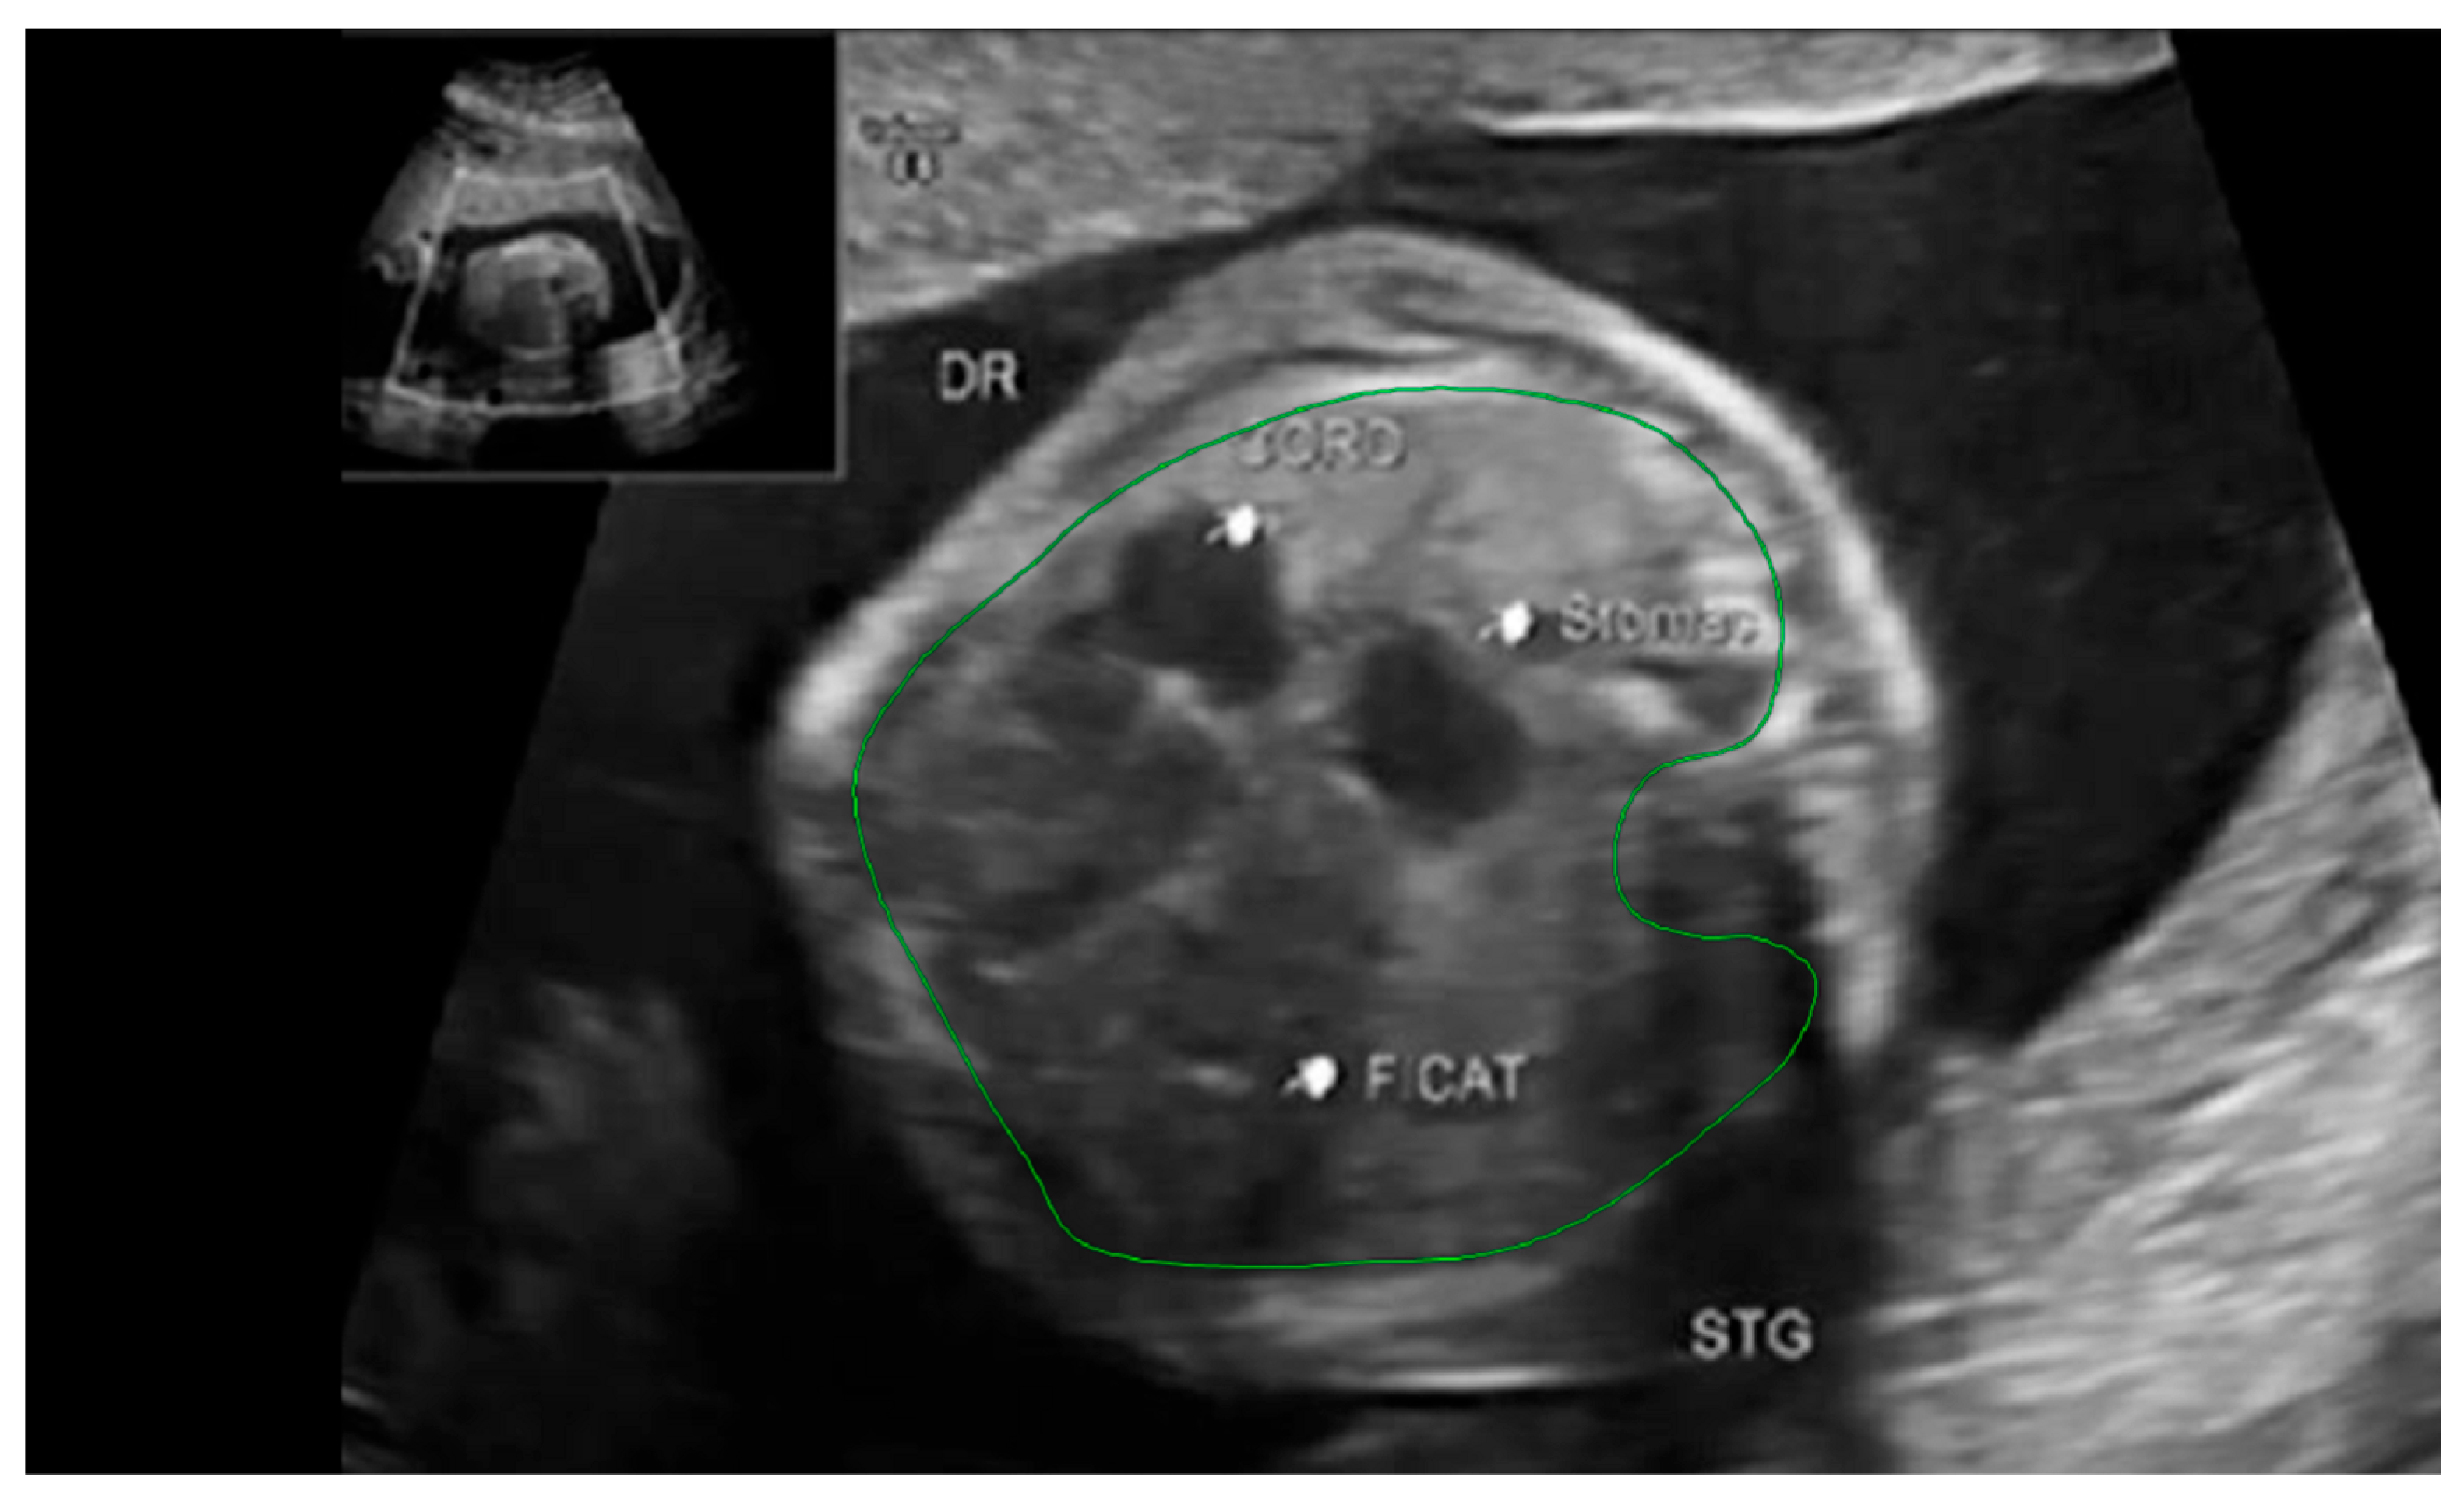

Fetal lung volume was calculated by using a new method to reduce the overestimation of the lung volume. The first step was tracing the lung area of both lungs on each slice. We then obtained the mean between every 2 consecutive slices and multiplied the value by the distance between them. Finally, we calculated the sum of all these values and obtained the TLV for each lung. For easier viewing of this parameter, we calculated the total lung volume ratio (TLVR) by calculating the ratio between our observed value and the expected lung volume values obtained from reference articles that measured standard values for lung volumetry using MRI. To be more precise, we looked at the studies of Meyers et al., Rypens et al., Osada et al., and Sefidbakht et al. [16,17,18,19] and calculated a mean from them that was used as our reference. Figure 1 and Figure 2.

Figure 1. MRI axial T2 weighted image of the fetus showing the tracing method for calculating the lung volume, using the RadiAnt DICOM Viewer program, version number 2022.1.1. The green line represents the lug area on the nonherniated side.

Figure 2. Ultrasound axial four-chamber image of the fetus showing the tracing method for calculating the LHR, using the RadiAnt DICOM Viewer program, version number 2022.1.1. The green line represents the lug area on the nonherniated side.